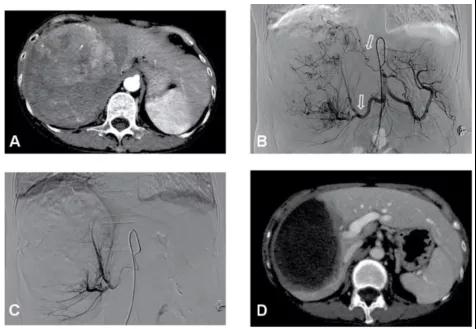

图4、该例肝右叶巨大肝癌合并门静脉右支癌栓(左图,箭头示癌栓),采用TACE治疗肝内肿瘤和放射性粒子治疗门静脉癌栓,术后19个月肝右叶肿瘤几乎完全坏死缩小,而粒子阻止了癌栓进展到主干,门静脉主干保持通畅(右图),现患者已生存5年。